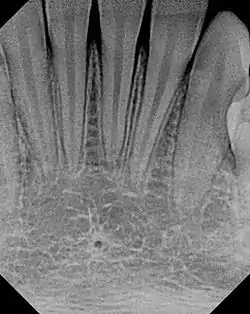

The small lingual foramen (black "hole" in lower portion of picture) as seen on a periapical radiograph of the anterior mandible.

The lingual foramen is a small opening situated on the lingual (tongue) side surface of the anterior mandible through which small blood vessels pass. The lingual foramen is usually situated in the midline of the internal surface of the mandible at the level of or superior to the mental spines.[1]